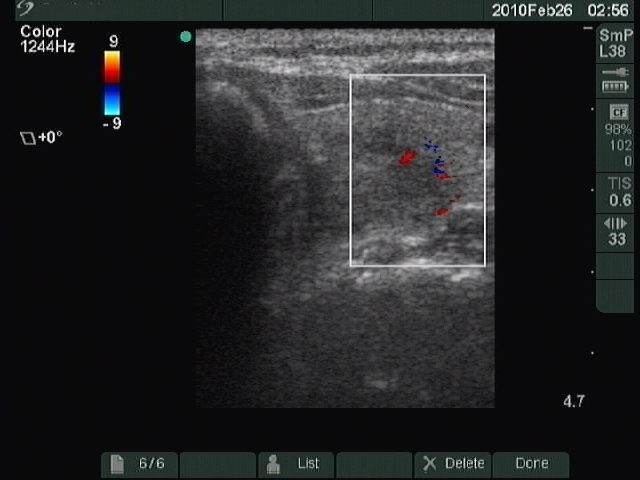

Benign nodular hyperplasia - Case 27. (ultrasonographic picture 6)

Right lobe, longitudinal scan

Left lobe, horizontal scan, color Doppler method. The left larger red patch corresponds to an intranodular vessel, while the other powder-like blue and red points are artifacts.